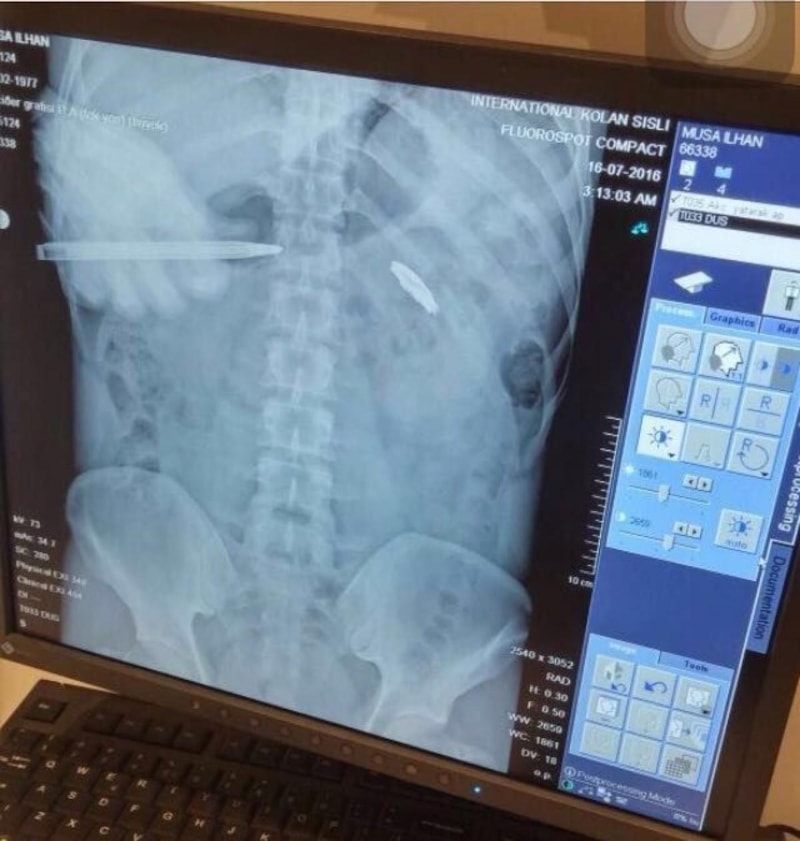

15 Temmuz darbe girişimi esnasında demokrasiye sahip çıkmak için sokağa çıkan Musa İlhan, hainlerin sıktığı kurşunla kalbinin 2 milimetre altından yaralandı.

Kurşunun vücudundan çıkarılmasının riskli olması nedeniyle 8 yıldır mermiyle yaşayan İlhan, "9 yıldır göğsümde gaziliğin nişanesini taşıyorum. Müslüman Türk milleti için gazilik nişan ise şehitlik düğündür. Çoğu zaman hayıflanıyorum keşke şehit olabilseydim diye. Cumhurbaşkanımız, Cumhur İttifakımız büyük bir özveriyle risk aldı. ‘Terörsüz Türkiye' inşallah başarılı olur. Bir ulus için, bir devlet için ayağındaki en büyük pranga terördür. Terörden kurtulan her ülke şahlanmıştır. İnşallah Türkiye Yüzyılı'nda terörden kurtulmuş ve şahlanmış Türkiye'yi bizlere görmek nasip olur. Büyük Türkiye'nin ayak seslerini bütün dünya hissediyor." dedi.

Fetullahçı Terör Örgütü'nün (FETÖ) 15 Temmuz 2016 tarihinde gerçekleştirdiği hain darbe girişiminin üzerinden 9 yıl geçti. Darbe girişiminde her yaştan vatandaş sokağa çıkarak darbeye ‘dur' dedi. O vatandaşlardan kimi şehit oldu kimi de yaralanarak gazilik mertebesine erişti. Demokrasiye sahip çıkmak için sokağa çıkan Musa İlhan da darbeye karşı duranlardandı. İlhan, trafikte seyir halindeyken 15 Temmuz hain darbe girişimini radyodan öğrendi. Vatan savunması için sokakta kalan Musa İlhan, korkusuz bir şekilde darbeci askerlerin karşısına dikildi. Darbecilerin kurşunlarının hedefi olan İlhan, kalbinin 2 milimetre altına isabet eden mermiyle yere yığıldı. Ağır yaralanan İlhan, çevredekiler tarafından hastaneye kaldırıldı. 4 gün yoğun bakımda kalan İlhan, 2 ay süren tedavinin ardından sağlığına kavuştu. Ancak cerrahi müdahale riskli olduğu için kurşun çıkarılamazken, 9 yıldır hainlerin sıktığı mermiyle yaşıyor.